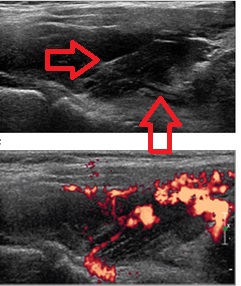

甲状腺に発生する血管腫は非常に稀で、日本の報告例もわずかです(日臨外会誌 72(3),579―583,2011)。

ケース④